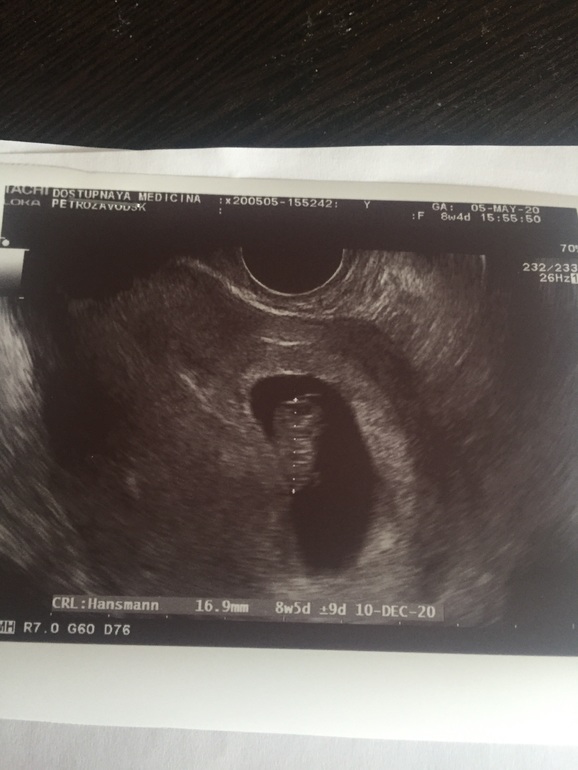

Хорошие новости 8,4 недель

Изменения и болезни во время БВ общем, я была на УЗИ 🤣

Это крайнее УЗИ перед скринингом.

Мне исключили дефект нервной трубки, что было в прошлый раз.

Так же, врач сказала , что порог в 8 недель , наиболее опасный пройден.

Прикопаться не к чему. Все отлично.